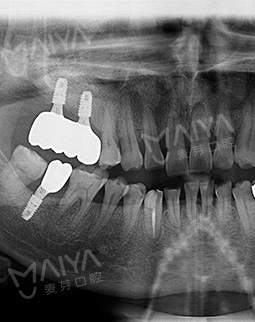

按照预约的时间,今天早早就来到了麦芽口腔,通过德国KAVO锥形束CT检查缺牙处牙槽骨的骨质密度、厚度,并分析牙周口腔健康后,郑院长根据我牙槽骨数据和口腔健康情况分析,采用MAC数字化精确种植,来恢复牙咬合功能的种植方案。

首先通过数字化精确影像采集测量患者牙床的骨质密度、牙槽骨本身的高度、宽度等条件,设计最佳力学种植点,同时发现神经血管,做到心中有数。在手术过程中,通过实时导航技术,控制种牙的深浅、避开口内危险区域,不仅减小了创口,平均种1颗牙耗时10分钟,减少了肿痛和出血量,缩短了种植牙时间,种植位置更准确,种植成功率更高,帮助了无数害怕疼痛的缺牙患者,轻松拥有一口好牙。

种牙手术结束后,苏伟说“完全没传说中要做手术那种恐慌,本以为手术过程中会感觉到疼痛,结果就像被蚊子叮了下,轻松就完成了,并且手术后也没有什么不良反应,感觉非常好。给郑院及麦芽的硕博智库专家团点赞!